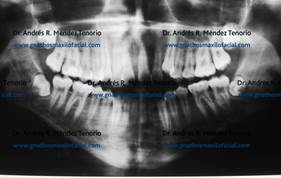

| Radiografías antes y después de la extracción | |